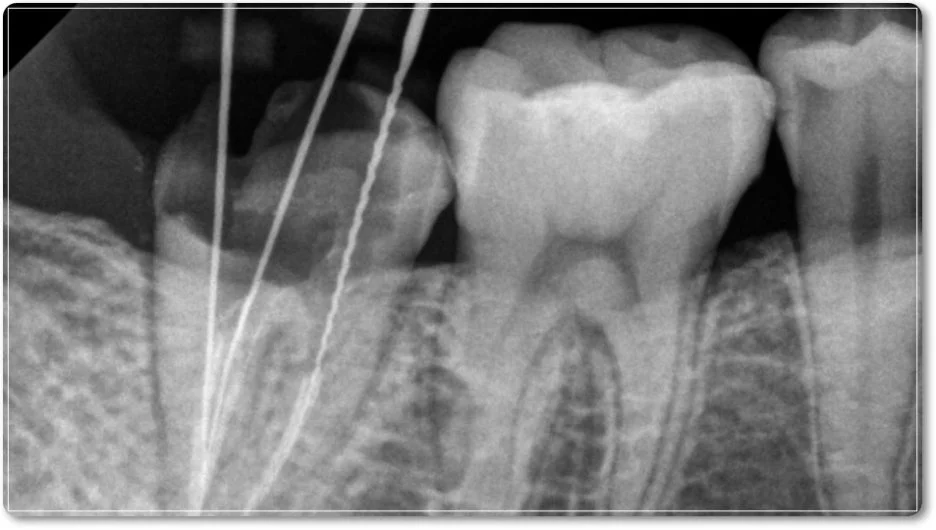

검사 결과 신경치료가 되어 있는 치아 뿌리 주변에 염증성 병소가 확인되어 최소한 재신경치료가 필요한 상황이었습니다.

치아 가운데 보이는 진하게 하얀 부분을 확인해보니 금속 기둥이 들어가 있을 가능성이 높아 보였습니다. 이런 기둥을 제거하는 과정에서 치아가 부러지는 경우도 적지 않아 비교적 까다로운 케이스에 속합니다.

꽤 오랜 시간 제거를 진행한 뒤 확인 차 엑스레이를 촬영해 보았는데, 생각보다 큰 변화는 보이지 않는 상태였습니다.

신경치료 과정에서 뿌리를 막고 있던 재료를 모두 제거하는 것 역시 쉽지 않은 작업입니다. 다행히 치아 뿌리 쪽 염증 부위까지 접근할 수 있었고, 방사선 촬영을 통해 해당 부분을 확인할 수 있었습니다.